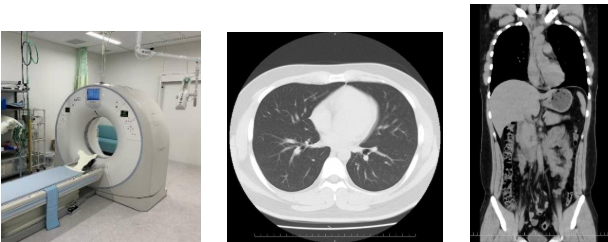

○ CT (Computed Tomography:コンピュータ断層撮影)

X 線を用いて体の輪切りの画像を撮影する検査です。ドーナツ状の機械に入り、体の周りを機械が回転し撮影していきます。

検査はベッドに寝た状態で行い、検査時間も短時間で終わります。

また得られた画像から 3D 画像などを作ることも可能です。

検査を行う際に金属類などを外していただく場合があります。ご協力よろしくお願いいたします。